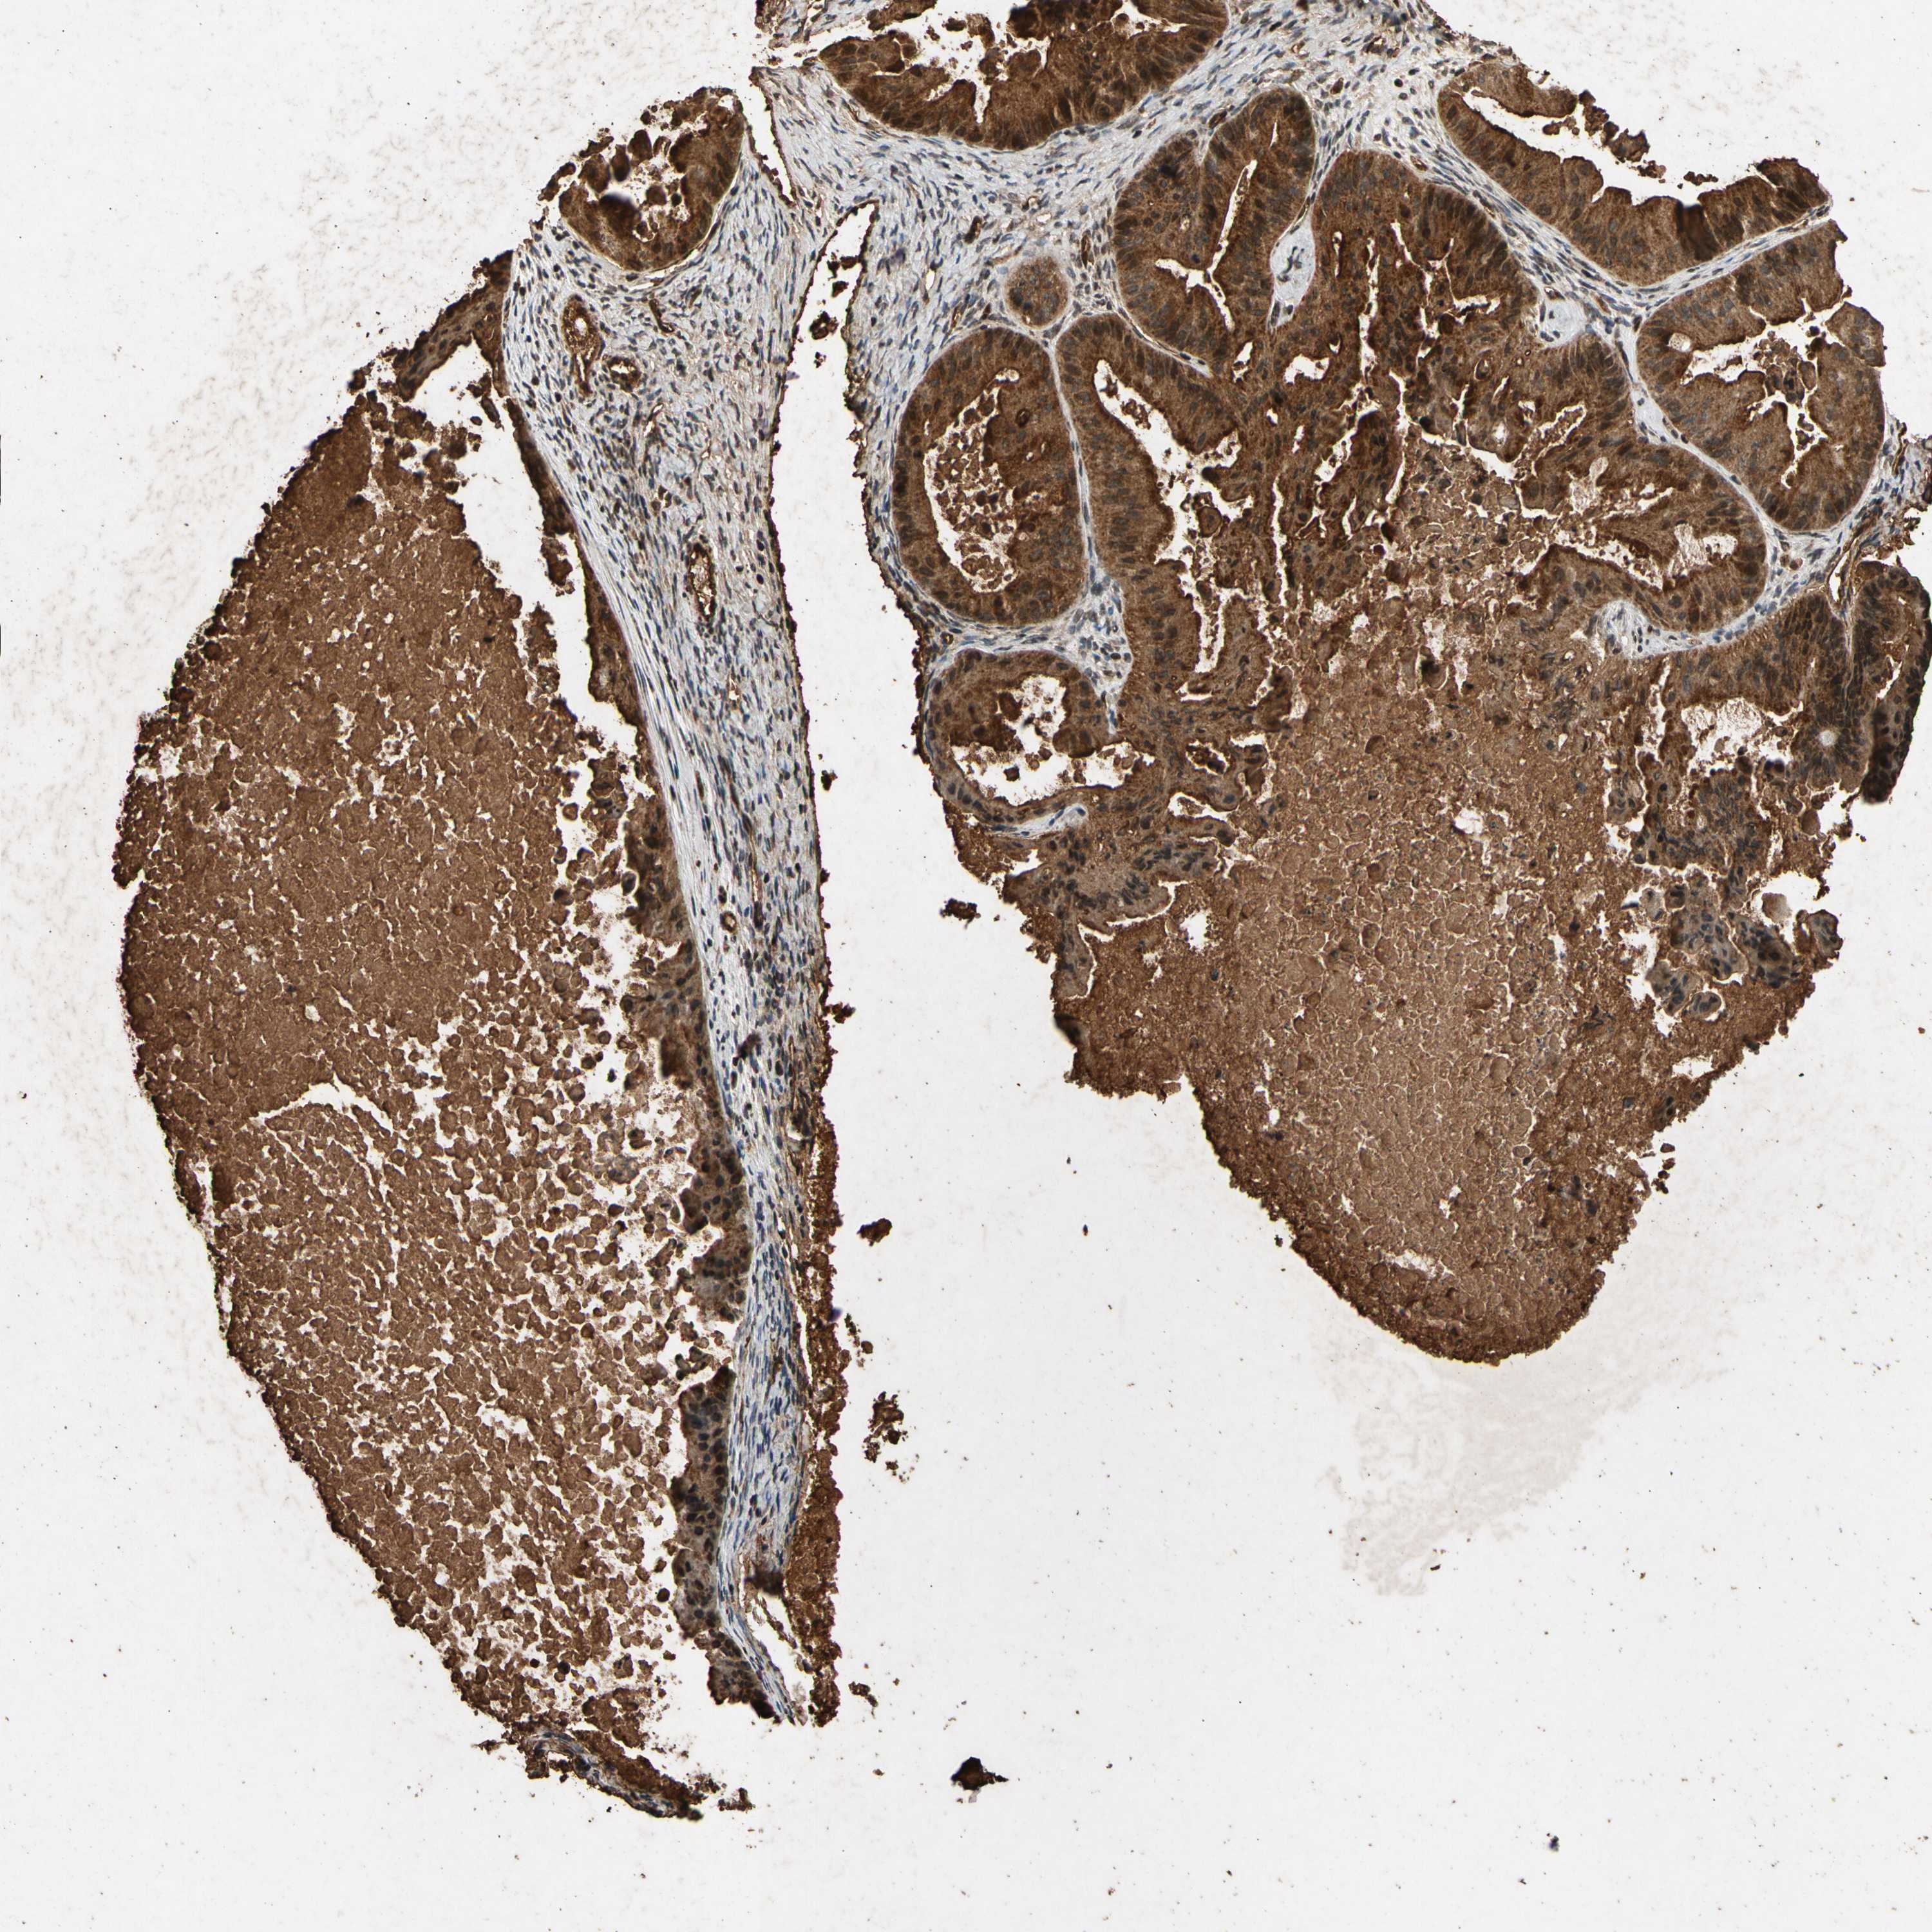

OVARIAN CANCER - Protein expressioni

A mouse-over function shows sample information and annotation data. Click on an image to view it in a full screen mode. Samples can be filtered based on level of antibody staining by selecting one or several of the following categories: high, medium, low and not detected. The assay and annotation is described here.

Note that samples used for immunohistochemistry by the Human Protein Atlas do not correspond to samples in the TCGA dataset.

Antibody stainingi

Antibody staining in the annotated cell types in the current human tissue is reported as not detected, low, medium, or high, based on conventional immunohistochemistry profiling in selected tissues. This score is based on the combination of the staining intensity and fraction of stained cells.

Each image is clickable and will lead to virtual microscopy that enables deeper exploration of all samples and also displays staining intensity scores, fraction scores and subcellular localization as well as patient and tissue information for each sample.

Antibody HPA000994

Antibody CAB008681

Cystadenocarcinoma, mucinous, NOS

Carcinoma, endometroid

Cystadenocarcinoma, serous, NOS

Carcinoma, NOS